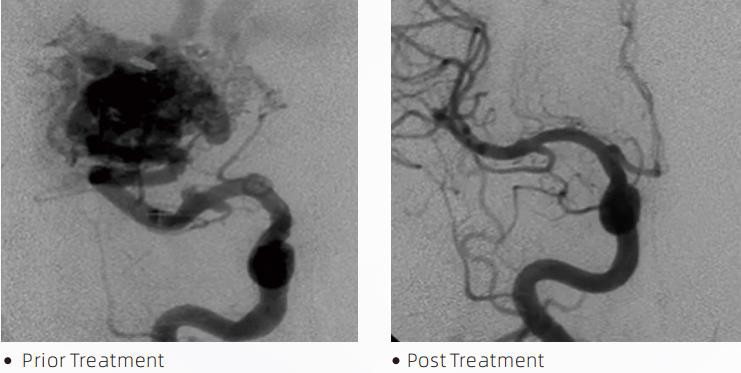

LavTMSıvı Embolik Sistem, serebrovasküler malformasyonların tedavisine yönelik girişimsel bir endovasküler tedavidir. Serebrovasküler malformasyon, intrakranyal kanamaya, serebral enfarktüse, serebral iskemiye ve diğer hastalıklara yol açabilen bir grup iyi huylu veya kötü huylu nörovasküler anormalliği ifade eder. Sıvı embolizasyon sistemi, özel bir sıvı madde enjekte edilerek anormal serebral kan damarlarını embolize eden, basit damar içi yerleştirme yoluyla uygulanan tıbbi bir cihazdır. Sıvı malzeme, kan damarlarında kontrollü bir doku embolisi oluşturur ve bu da serebrovasküler malformasyonların hastalar üzerindeki etkisini azaltabilir. Embolizasyon bölgesine erişmek için nörovasküler yapıda kullanılması endike olan DMSO uyumlu bir dağıtım mikro kateteri kullanılır. Lava sıvı embolik ajan, DMSO (dimetil sülfoksit) içinde çözünmüş EVOH (etilen vinil alkol) kopolimerinden ve floroskopi altında görselleştirme için kontrast sağlamak üzere süspanse edilmiş mikronize tantal tozundan oluşan yapışkan olmayan bir sıvı embolik ajan sistemidir. LavTMLAVA-12, LAVA-18 ve LAVA-34 olmak üzere üç ürün formülasyonu mevcuttur. LAV-12: Distal mikro damarları beslerken ve küçük besleyiciler yoluyla önerilir. LAVA-18: Besleme pedikül enjeksiyonlarının nidusa yakın olarak gerçekleştirileceği durumlarda önerilir; LAV-34: Daha yüksek akışlı ve daha büyük fistül bileşenlerin embolize edilmesi için önerilir.